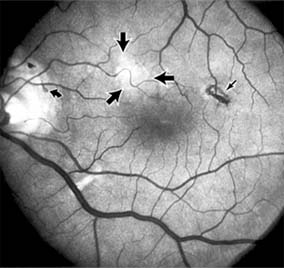

MACULAR EDEMA

Retinal edema involving the macula may be associated with a variety of intraocular inflammatory diseases, retinal vascular diseases, intraocular surgery, inherited or acquired retinal degenerations, medications, macular membranes, or unknown causes. Macular edema may be diffuse, with nonlocalized intraretinal fluid causing thickening of the macula. When edema fluid accumulates in honeycomb-like spaces of the outer plexiform and inner nuclear layers, it is called cystoid macular edema. On fluorescein angiography, fluorescein dye leaks from the perifoveal retinal capillaries and accumulates in a flower-petal pattern about the fovea (Figure 10-4).

Figure 10-4

Figure 10-4: Flower-petal pattern of fluorescein dye in a patient with cystoid macular edema after cataract surgery.